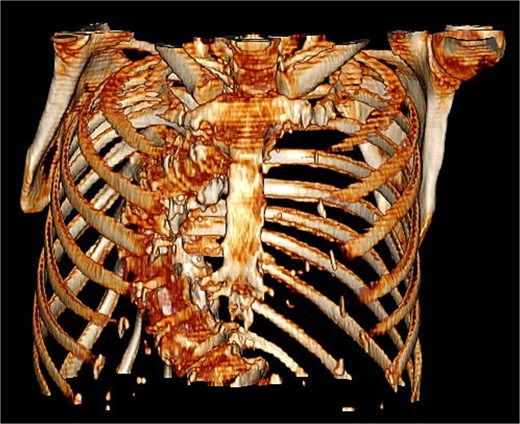

A 71-year-old female was referred to the heart team for elective minimally invasive MVR and septal myectomy. She presented with severe mitral regurgitation and hypertrophic obstructive cardiomyopathy (HOCM). Her body surface area was 1.51 m2, and BMI was 29.42. Critically, her scoliosis had a Cobb angle of 80° (Fig. 1), qualifying as extremely severe.

Coronal computed tomography (CT) with measurement of the cobb angle.